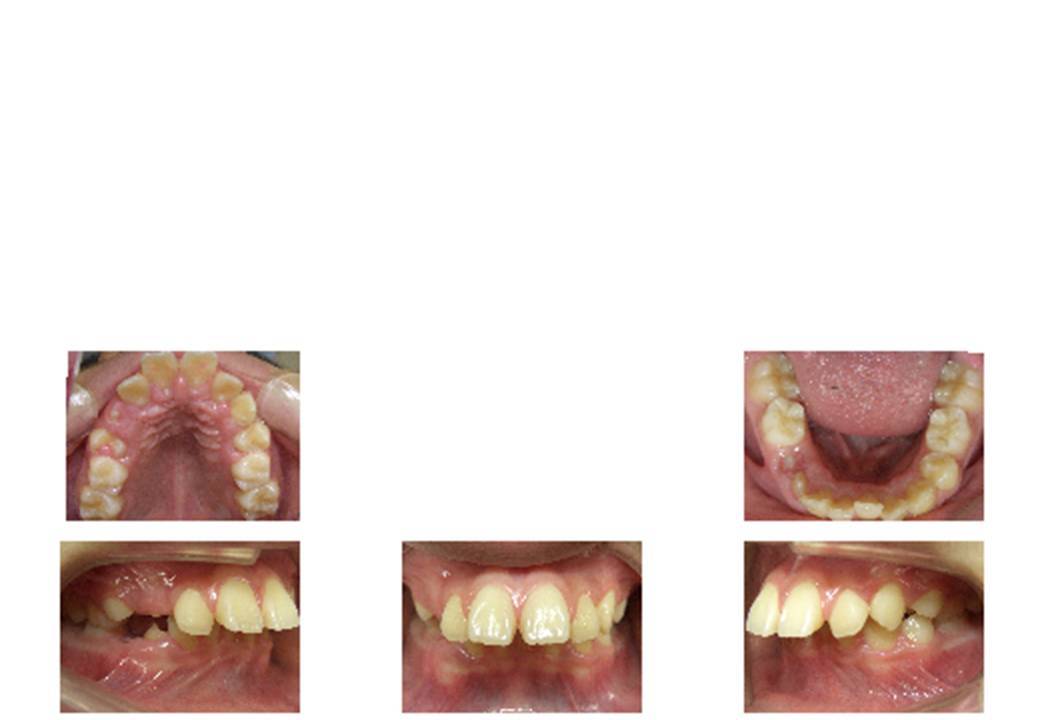

子供の出っ歯症例

出っ歯という言葉。上の前歯が出ている歯並びの通称です。

詳しく言うと、下の前歯よりも上の前歯の方が著しく前にある、ということです。

この言い方は、より目立つ上の歯にフューチャーしてますが、この歯並びの根本的な原因は下の顎が凹んでいることにあります。

正確な言い方としては、「下顎引っ込み」です。

一方で子どもの場合は、下顎の成長をコントロールできるので、「下顎引っ込み」という名称で間違いありません。

子供の出っ歯

下顎を前に成長させることにより出っ歯を解消します。永久歯が揃ったらブラケット装置にて矯正します。